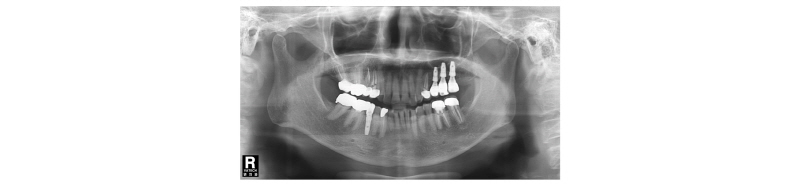

Fig. 32. Periapical x-ray view. Final prosthesis. |

70세의 여자환자로 상악에 사용하던 부분틀니가 불편하다고 호소하시며 내원하였다. 부분 틀니의 지대치인 상악 좌측 견치 또한 보철물 하방으로 우식이 진행되어 보철물 제거후 우식치료 후 보철물을 재제작하여 장착하기로 계획하였다. 치아가 결손되어 있던 상악 좌측 소구치와 대구치 부위는 임플란트 식립(#24i-26i, 27i)을 통한 고정성 보철물 수복을 계획하였다(Fig. 19). 장기간의 부분틀니 장착으로 인해 임플란트 식립 예정 부위의 심한 치조제 흡수가 관찰되었으며 특히 소구치 부위가 가장 흡수 정도가 심하였다(Fig. 20). 전층판막 형성 후 상악 좌측 제 1 소구치 부위는 치조정에서 약 2 mm 정도의 매우 좁은 치조제 폭경이 확인되었다(Fig. 21). 먼저 상악 좌측 제 1 소구치 부위 치조정에 horizontal intraosseous groove를 작게 형성한 후 협측골에 근, 원심 양측에 vertical intraosseous groove를 형성하였다(Fig. 22). Chisel을 이용하여 협측 골판을 조금 확장시킨 다음 spreader drill (RS kit, Dentium, Korea)을 단계적으로 이용하여 충분히 확장시켜 임플란트 식립을 위한 공간을 확보하였다(Fig. 23). 분리된 협,설측 골판 사이 공간으로 Ø4.3 × 10 mm (Implantium, Dentium, Korea) 임플란트를 식립하였다(Fig. 24). 상악 좌측 대구치 부위는 상악동 거상술(측방접근법)을 시행하여 #26i, 27i : Ø4.3 × 10 mm, Ø4.8 × 10 mm (Implantium, Dentium, Korea)를 식립하였다(Fig. 25). 식립된 24i 임플란트와 협,설측 골판 사이의 gap에 합성골 (Osteon II, Xenoss, Korea)을 적용한 다음 협측 골판 상방에 콜라겐함유 합성골(Osteon II Collagen, Xenoss, Korea)을 추가적으로 적용하였고 식립된 26i, 27i 임플란트 부위의 협측골 두께가 얇아서 협측골 상방에도 콜라겐함유 합성골(Osteon II Collagen, Xenoss, Korea)을 적용하였다(Fig. 26). 골이식재 상방에 흡수성 교원질 차폐막(Collagen, Xenoss, Korea)을 피개한 후 감장절개를 통해 장력없이 봉합하였다(Fig. 27, 28). 약 10일 후 발사 시의 임상소견으로 정상적으로 치유가 잘 진행되었다(Fig. 29). 술 후 파노라마 방사선 소견으로 치조제 분할술을 통해 식립된 24i 임플란트와 상악동 거상술(측방접근법)을 시행하여 식립된 26i, 27i 임플란트가 확인되었다(Fig. 30). 4개월 치유 후 이차 수술 시 전층 판막거상 후 협측으로 충분히 증가된 치조제 폭경과 식립된 임플란트 주위에 이식한 골이 혼화되어 치유된 양상이 확인되었고 치유지대주를 연결하였다(Fig. 31). 이차 수술 후 치유가 정상적으로 진행되어 통법에 따라 보철 수복하였다. 보철물 수복 직후 방사선 사진 소견으로 식립된 24i 임플란트의 변연골 위치가 확인되었다(Fig. 32). 보철물 장착 후 1년 후 방사선 소견에서 임플란트 주위 변연골이 안정적으로 잘 유지되고 있었다(Fig. 33). 보철물 장착 4년 후 follow- up 결과 임플란트 주위 치은이 약간 퇴축된 양상을 보였으나 임상적으로 특이한 소견이 관찰되지 않았고 방사선 소견에서 임플란트 주위 변연골이 안정적으로 잘 유지되고 있음을 확인하였다(Fig. 34-36).